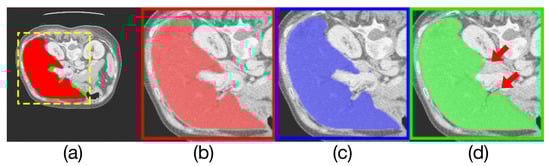

Similarly, Table 3 compares the spleen segmentation performance on MRI images, where Render U-Net had the best performance. The output of the model and the manually annotated result are compared in Figure 10. Our proposed network increased mIoU by over 0.1672 [10], and increased the Dice coefficient by 0.0981, increased precision by 14.98 percentage points, and increased the recall rate by 4.29 percentage points.

Figure 10. Comparison of model outputs and ground truth. (a) is composed of the other three figures above are stacked from top to bottom, where the predicted extra areas are clearly seen. (b) is the manually annotated result. The blue region in(c) is the output of Render U-Net. The green region in (d) is the output of U-Net. Some areas with incorrect predictions are indicated with the red arrows in the figure.